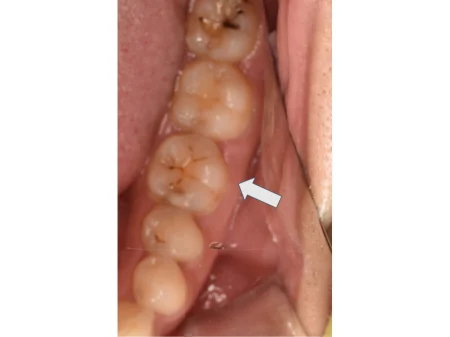

セラミック 2023.0330代女性「歯が痛い」徹底的に虫歯除去した部分を、白くてなじみがいいセラミック素材の詰め物「E-maxインレー」で治療した症例